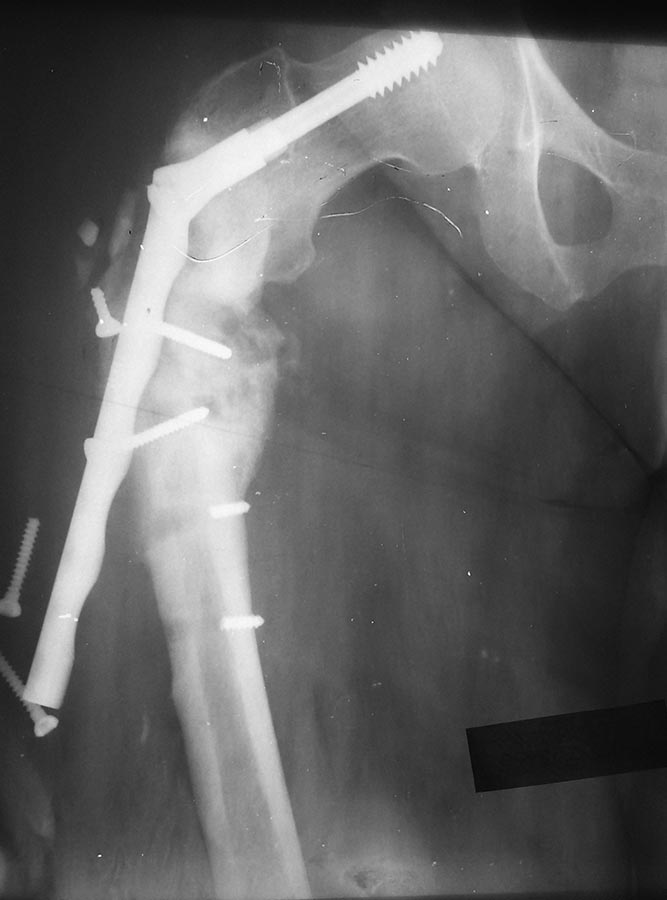

Повторный перелом подвертельной зоны с несостоятельностью метфиксатора. Что посоветуете? |

Больная 39 лет. Полная. В анамнезе тяжёлая ЧМТ с левосторонним гемипарезом и дисфазией. Больная впервые оперирована мной 2.5 года назад. Имел место оскольчатый подвертельный перелом.Поставил подвертельную пластину Double medical.Но поскольку у больной имеет место левосторонний гемипарез и дисфазия после перенесённой ЧМТ, она стала сразу ходить с полной нагрузкой. В итоге через полгода перелом метфиксатора.При повторной операции был установлен DHS на длинной ножке. Спустя год смотрел снимки - выраженная костная мозоль. И вот вчера после предварительного падения, я снова с ней встретился. По сегодняшним результатам СКТ перелом свежий. Я предлагаю удадение DHS, установку PFN с возможной костной пластикой.Коллеги, что посоветуете?

Выглядит как типичное несращение такой локализации. Да, удалить и закрыто заштифтовать, хорошо восстановив ось, то есть не оставляя варус. Костная ластика не нужна.

В общем, я обещал выложить снимок.

После доступа из полости раны получено что-то вроде тканевого детрита (ИМХО). Это было взято на посев. Далее DHS был повторно дистально прикручен к кости.Само место перелома не открывалось. На операции присутствовал в качестве наблюдателя.